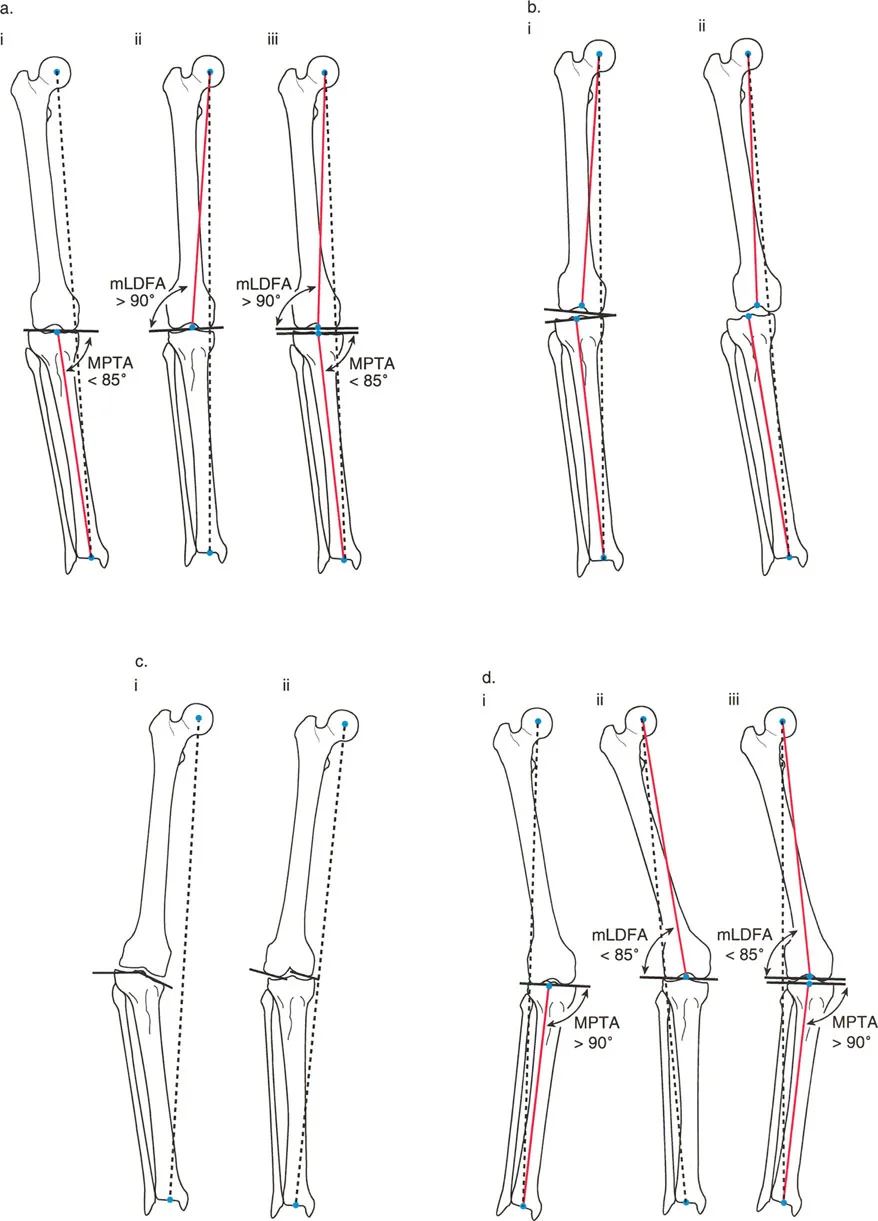

زوايا المفاصل في المستوى الأمامي: دقة التفاصيل

إن معرفة المحور الميكانيكي العام هو خطوة أولى، ولكن لتصحيح أي تشوه، يجب أن نعرف أين يقع هذا التشوه بالضبط. هل التقوس أو الفحج يأتي من الورك، أو الركبة، أو الكاحل؟ للإجابة على هذا السؤال، نقوم بتقييم زوايا توجيه المفاصل الفردية في المستوى الأمامي (الرؤية من الأمام).

توجيه مفصل الركبة (المستوى الأمامي)

خط مفصل الركبة ليس عمودياً تماماً على المحور الميكانيكي للطرف السفلي. بل هو في الواقع مائل بحوالي 3 درجات فحج (valgus) بالنسبة للمحور الميكانيكي للفخذ، و3 درجات تقوس (varus) بالنسبة للمحور الميكانيكي للساق. هذا الانحراف البسيط هو تكيف بيوميكانيكي مذهل سنشرحه لاحقاً.

الزاوية الفخذية البعيدة الوحشية الميكانيكية (mLDFA)

هي الزاوية الوحشية (الخارجية) المتكونة بين المحور الميكانيكي لعظم الفخذ وخط مفصل الفخذ البعيد (خط مماس لأبعد نقطتين في لقمتي الفخذ الإنسية والوحشية).

* القيمة الطبيعية المقبولة لـ mLDFA هي 87.5 درجة ± 2 درجة.

* ملاحظة سريرية: عظم الفخذ البعيد يكون عادةً في درجة طفيفة من الفحج بالنسبة لمحوره الميكانيكي.

الزاوية الظنبوبية القريبة الإنسية الميكانيكية (MPTA)

هي الزاوية الإنسية (الداخلية) المتكونة بين المحور الميكانيكي لعظم الساق وخط مفصل الساق القريب (خط يمر عبر العظم تحت الغضروفي للسطح العلوي لعظم الساق).

* القيمة الطبيعية المقبولة لـ MPTA هي 87 درجة ± 2 درجة.

* ملاحظة سريرية: عظم الساق القريب يكون عادةً في درجة طفيفة من التقوس بالنسبة لمحوره الميكانيكي.

تساعد هذه الزوايا الأستاذ الدكتور محمد هطيف على تحديد ما إذا كان التشوه في الركبة مصدره عظم الفخذ أو عظم الساق، وهو أمر حاسم لتخطيط العمليات الجراحية مثل قطع العظم (Osteotomy) أو استبدال مفصل الركبة.